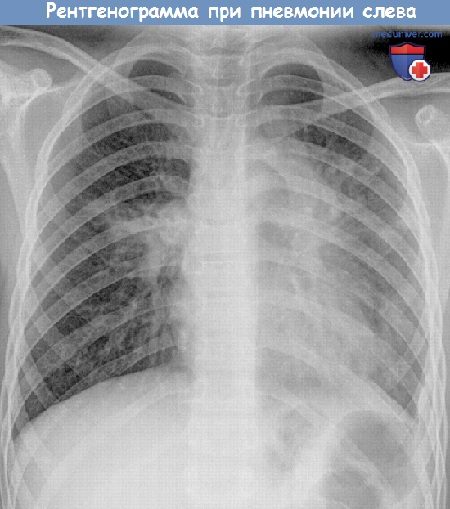

Рентген грудной клетки для диагностики пневмонии

Для точной диагностики больного обязательно отправляют на рентген грудной клетки. Про наличие пневмонии говорит скопление инфильтрата, который может занимать небольшой сегмент или целое легкое.